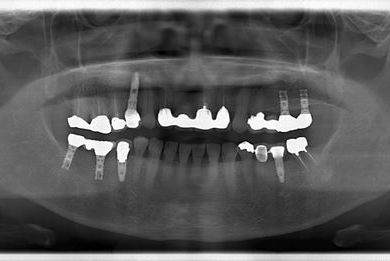

骨再生スピードインプラント治療+セラミック治療

| 治療方針 | 骨再生法によりインプラント治療を可能にする。抜歯と同時にインプラント埋入を行い、治療期間を短縮する。 | ||||||||||||||||||||||||||||||||

| 治療内容 | インプラント3本(抜歯即日スピードインプラント、GBR)、メタルボンドセラミッククラウン4本 | ||||||||||||||||||||||||||||||||